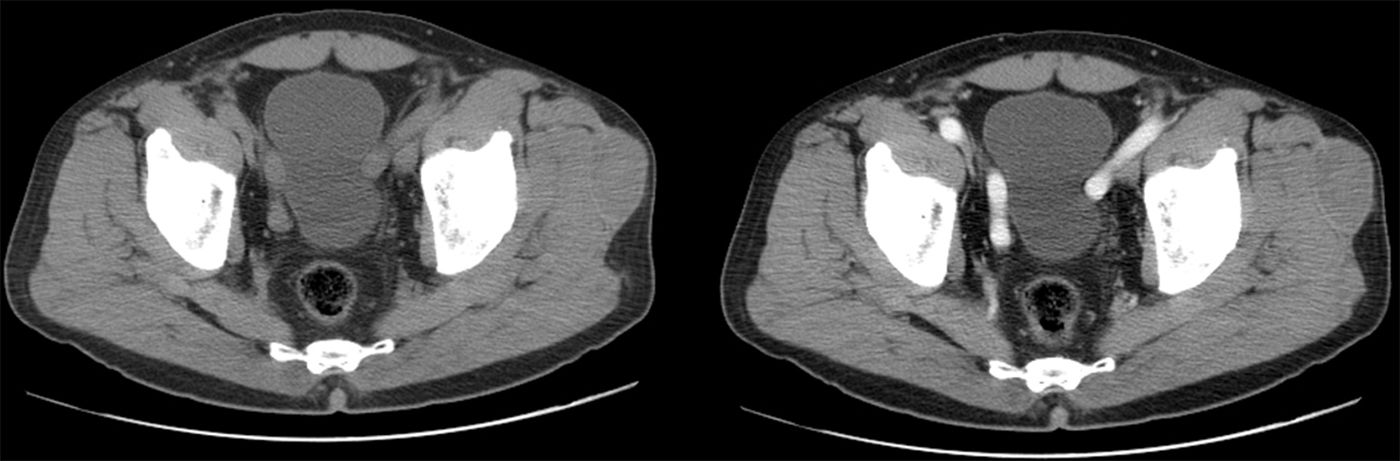

We aim to review the characteristics of Morel-Lavallée lesions and to evaluate their treatment.

Material and methodsWe retrospectively reviewed 17 patients (11 men and 6 women; mean age, 56.1 years, range 25–81 years) diagnosed with Morel-Lavallée lesions in two different departments. All patients underwent ultrasonography, 5 underwent computed tomography, and 9 underwent magnetic resonance imaging. Percutaneous treatment with fine-needle aspiration and/or drainage with a 6–8F catheter was performed in 13 patients. Two patients required percutaneous sclerosis with doxycycline.

ResultsAll patients responded adequately to percutaneous treatment, although it was necessary to repeat the procedure in 4 patients.

ConclusionsRadiologists need to be familiar with this lesion that can be treated percutaneously in the ultrasonography suite when it is not associated with other entities.